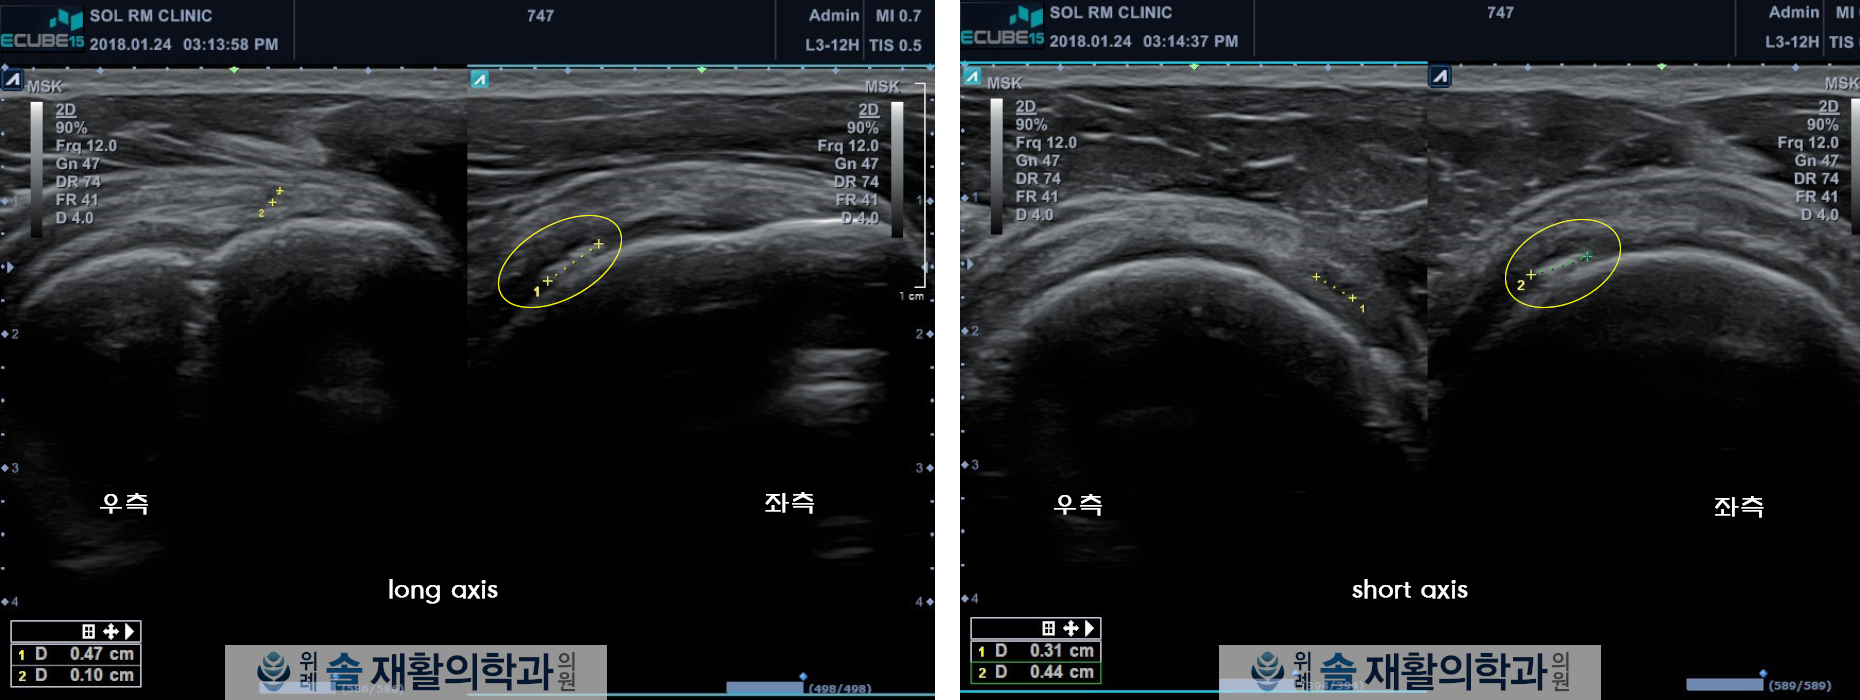

초음파에서도 2cm 길이의 석회성 병변이 회전근개 극상근에 확인되었으며, 압통 부위와 일치하는 소견이 확인되어 회전근개 극상근의 석회성 건염으로 진단하였습니다.

이 후 통증 감소 및 석회성 병변의 정상화를 위해 조직재생 주사 3회와 체외충격파 치료 8회를 시행하였고, 치료 한달만에 통증은 거의 없을 정도로 ㅎ조넞되었고, 치료 두달 후 확인한 초음파 검사상 석회성 병변의 대부분이 소실됨이 확인되었습니다.